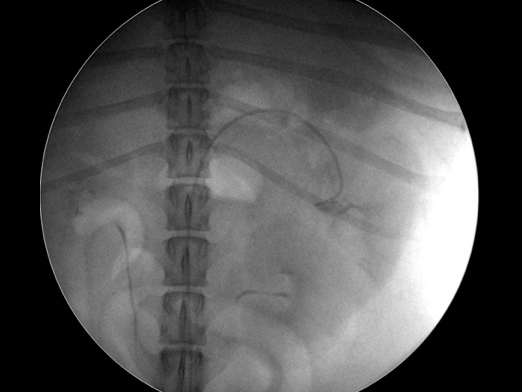

カテーテルを目的臓器まで挿入している様子